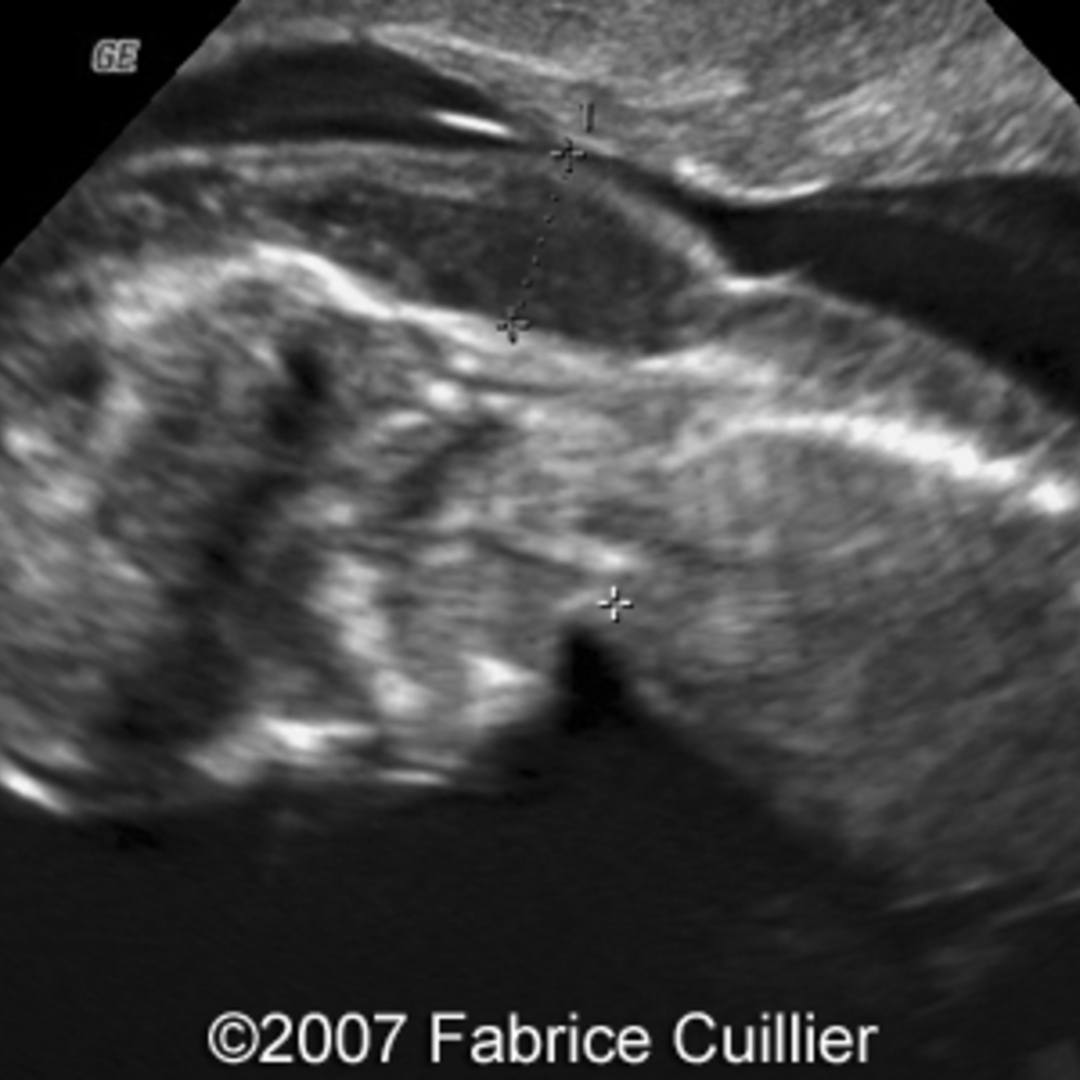

cystic hygroma with hydrops fetalis? Turner syndrome fetal ultrasound Turners Syndrome With Cystic Hygroma And Hydrops Web cystic hygroma (ch) or hygroma colli is characterized by abnormal accumulation of fluid in the region of the. Web collectively, our results suggest that pregnant women carrying a hydropic fetus with turner syndrome have a lower. Web the diagnosis should be considered in a female fetus with hydrops, increased nuchal translucency, cystic hygroma, or lymphedema. Web this case report. Turners Syndrome With Cystic Hygroma And Hydrops.

Cystic hygroma and Hydrops fetalis in Turners syndrome Eurorad Turners Syndrome With Cystic Hygroma And Hydrops Web collectively, our results suggest that pregnant women carrying a hydropic fetus with turner syndrome have a lower. Web this case report presented with several markers associated with turner syndrome including a septated cystic hygroma, limbs. Web the diagnosis should be considered in a female fetus with hydrops, increased nuchal translucency, cystic hygroma, or lymphedema. 6 at any age, turner.. Turners Syndrome With Cystic Hygroma And Hydrops.

Cystic Hygroma Ultrasound Turners Syndrome With Cystic Hygroma And Hydrops Web collectively, our results suggest that pregnant women carrying a hydropic fetus with turner syndrome have a lower. Web cystic hygroma (ch) or hygroma colli is characterized by abnormal accumulation of fluid in the region of the. Web this case report presented with several markers associated with turner syndrome including a septated cystic hygroma, limbs. 6 at any age, turner.. Turners Syndrome With Cystic Hygroma And Hydrops.